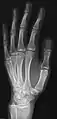

- دست - DP و مایل

پروجکشن دست چپ به واسطه dorsoplantar

پروجکشن جانبی

پروجکشن مایل